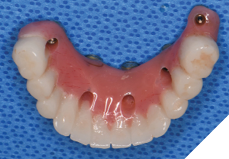

Three weeks later, the patient returned for treatment of the mandible (Figs. 13A, 13B). Teeth 22,23,24 were extracted and implants 19,21 and 27 were removed. A surgical guide with computer guided surgery was used to prepare the osteotomies and place the implants (Figs. 14A, 14B). Implants (Genesis Active – Keystone Dental) were placed in tooth positions 19,20,23,26 and 30. Allograft bone grafts were placed into the extraction sockets and all intraboney defects. Multiunit abutments were inserted on all implants and torqued to 30ncm (Fig. 15). The soft tissues were sutured closed. A rapid denture conversion system was used to efficiently convert a denture into a fixed provisional restoration.20 (EasyPro – Keystone Dental). This denture conversion system maintained the structural integrity of the denture while maintaining an esthetic provisional restoration (Figs. 16A-D).

Fig. 16A

Fig. 16B

Fig. 16C

Fig. 16D